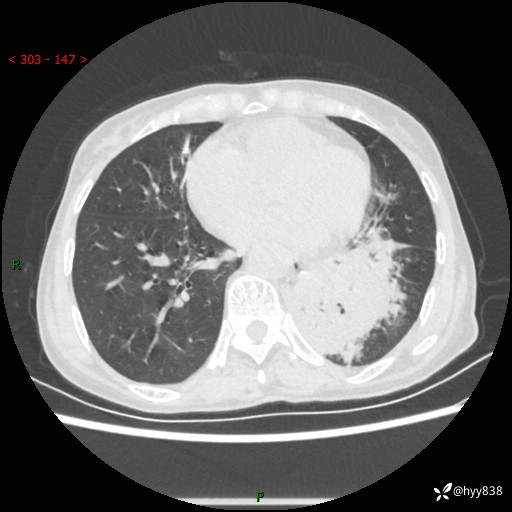

胸部CT平扫+增强